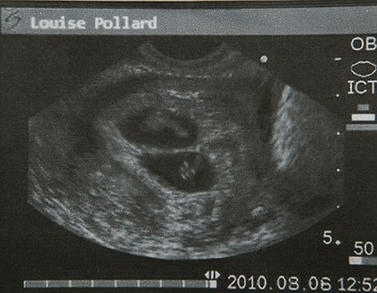

波拉德表示,她是本月6日在英國(guó)曼徹斯特一家私人診所做的超聲波檢查,影像資料顯示,她已經(jīng)成功受孕8周而且懷的是雙胞胎。自今年6月上旬波拉德公開承認(rèn)已答應(yīng)為奧馬爾夫婦代孕以來,她一直是英國(guó)媒體關(guān)注的焦點(diǎn)之一。

2010年8月6日,超聲波檢查顯示波拉德懷的是雙胞胎。